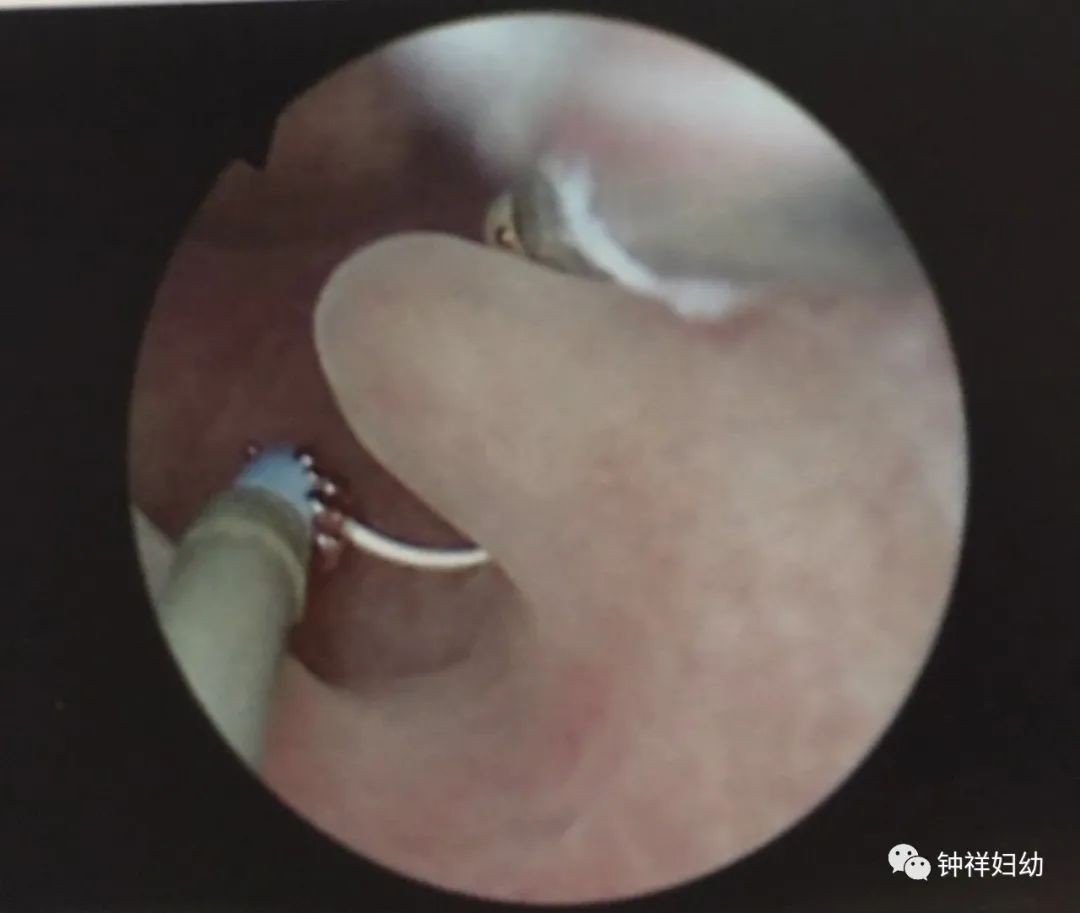

2、宫腔镜检查及病理组织学诊断:宫腔镜检查及镜下切除内膜息肉行病理学检查是诊断子宫内膜息肉的金标准。

②宫腔镜下子宫内膜息肉切除术:主要适用于绝经前有症状、合并不孕症及辅助生殖技术治疗前、有恶变高危因素、息肉直径>1.5cm、复发性、药物治疗效果不佳及绝经后子宫内膜息肉。需要保留生育功能的患者,宫腔镜下行子宫内膜息肉切除术时,注意保护周围子宫内膜;无保留生育功能需求的女性,尽可能彻底切除息肉,减少复发率。